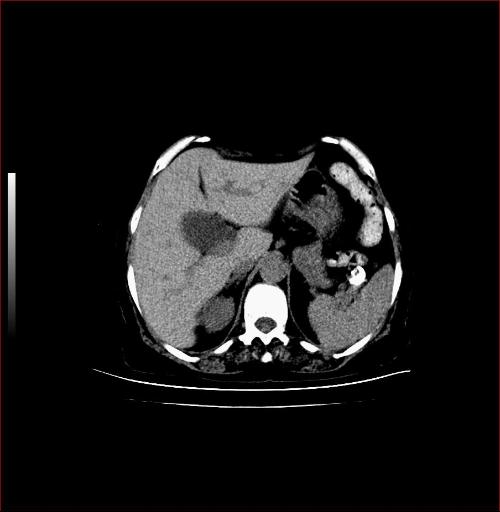

胆囊B超

胆囊B超,胆囊

胆囊

胆囊切除

胆囊图片